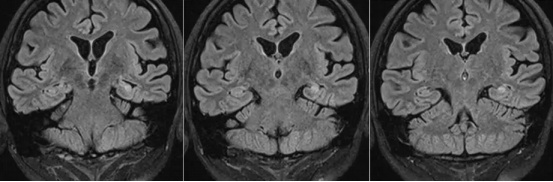

经头颅磁共振检查,发现存在左侧海马硬化、颞叶萎缩。至此,患者的诊断基本明确了,符合“颞叶癫痫”的诊断。

当然,这只是比较典型的案例,临床上可能会有一些发作较少或症状较轻的患者的脑电放电通过头皮脑电图很难抓到,需要反复检查、进行长程的脑电图检查或颅内电极脑电图才能明确。其次,我们要进行头颅磁共振检查,因为磁共振可以帮助我们发现癫痫的病因。在癫痫患者的检查中,我们可以发现各种各样的结构性异常,除了小陈那样的海马硬化,还可以见到如下病变: